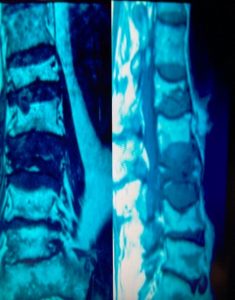

Τα Οστεοπορωτικά Κατάγματα της Σπονδυλικής Στήλης, που είναι και το κύριο αντικείμενο αυτής της μελέτης, έχουν σαν αποτέλεσμα την Κυφωτική και Σκολιωτική παραμόρφωση της (εικόνα 1 α,β) . Οι μεταβολές αυτές συνοδεύονται όπως εύκολα γίνεται αντιληπτό με έντονο πόνο σε όλη την έκταση της Σπονδυλικής Στήλης.

Εικόνα 1 α,β : Μαγνητική Τομογραφία της Σπονδυλικής Στήλης, προσθιοπισθία (coronal) και οβελιαία (sagittal) λήψη, Ακολουθία Τ2. Παρατηρείται η ύπαρξη πολλών οστεοπορωτικής αιτιολογίας καταγμάτων, συνεπεία των οποίων έχει προκληθεί σκολιωτική και κυφωτική παραμόρφωση της Σπονδυλικής Στήλης.